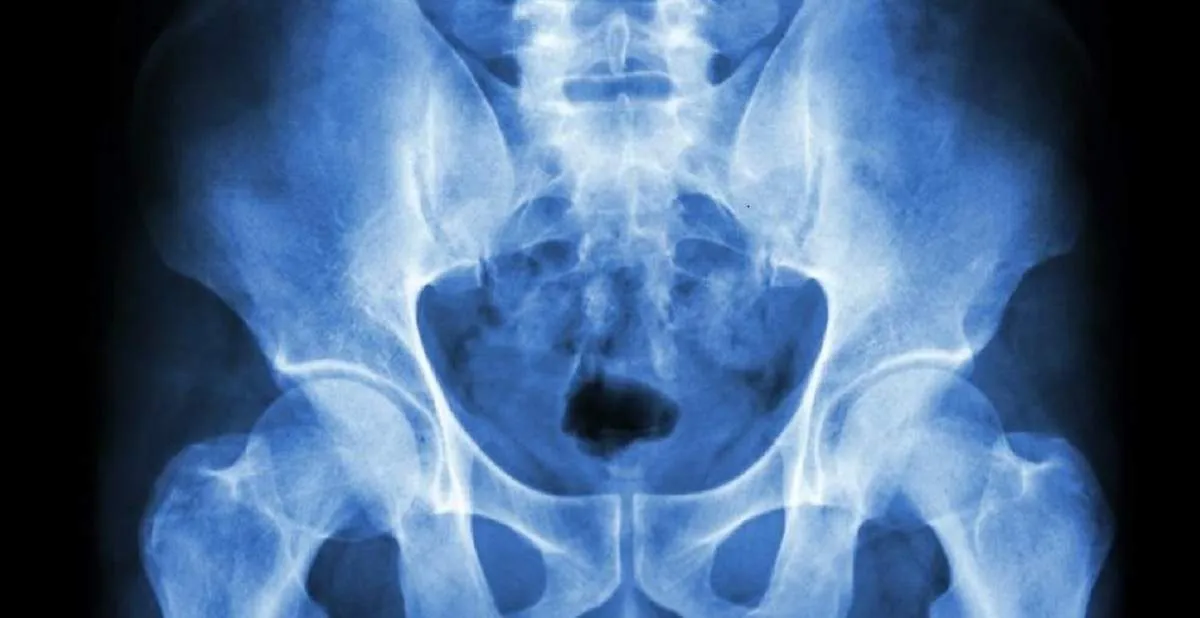

La disfunción de la sínfisis del pubis (osteopatía del pubis o SPD, por sus siglas en inglés) es el término que se usa para describir el dolor que se experimenta en la parte posterior, frontal y lateral de la pelvis durante el embarazo. El dolor a menudo se siente debajo de la barriga, directamente sobre el hueso púbico, alrededor de los lados de las caderas y en la espalda baja.

En la Osteopatía de Pubis se suman todas las patologías, pudiendo apreciarse alteraciones inflamatorio-reparadoras a nivel del hueso púbico, tanto en la inserción de los músculos abductores como abdominales y asociados a una pared-suelo abdominal frecuentemente debilitada.